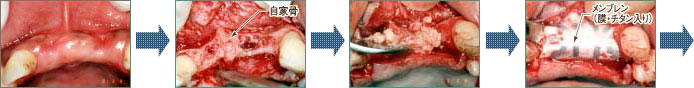

- 術前

- 内側の骨がボロボロに

なっている - つぶした骨を移植する

- メンブレン膜をはめる(チタン入り)

- 縫合する